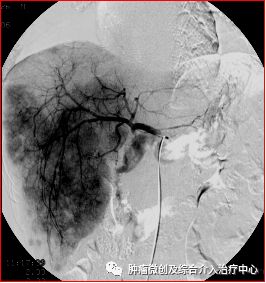

图1. 局麻后经大腿根股动脉穿刺置入导管至肝动脉内,创口约棉签样大小,行肝动脉造影寻找肿瘤及其责任血管。

图5、6. 一肝癌患者,栓塞前造影显示肝右叶巨大团块样肿瘤染色(图中发黑处),通过3次肝动脉化疗栓塞,肿瘤不再显影,较前明显缩小。